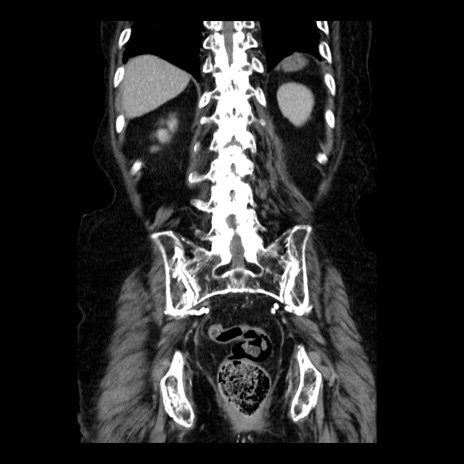

症例14(冠状断像)

【症例】 90歳代女性

【主訴】 腹痛・嘔吐

【現病歴】今朝から左側腹部痛を認めた。 経過観察していたが、嘔吐を認めたため来院。

【既往歴】 子宮癌術後

【身体所見】 意識清明、BP 127/54mmHg、P 98bpm Sp02 95%(RA)、BT 35.8°C、腹部平坦・軟腸ぜん動音聴取良好、右下腹部圧痛(+) 反跳痛なし

【データ】WBC 9800、CRP 0.46